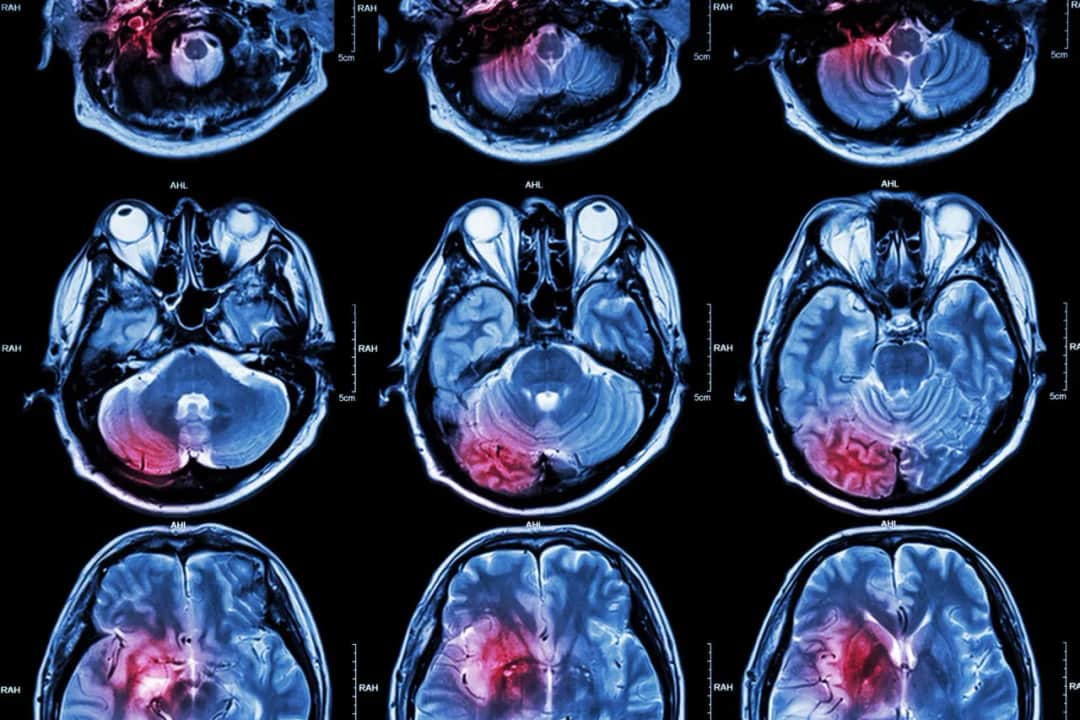

Objawy udaru móżdżku i skuteczne metody leczenia – co musisz wiedzieć

Poznaj objawy udaru móżdżku, przyczyny, metody leczenia i rehabilitacji. Dowiedz się, jak reagować w przypadku udaru i jakie są rokowania. Wszystko, co musisz wiedzieć.